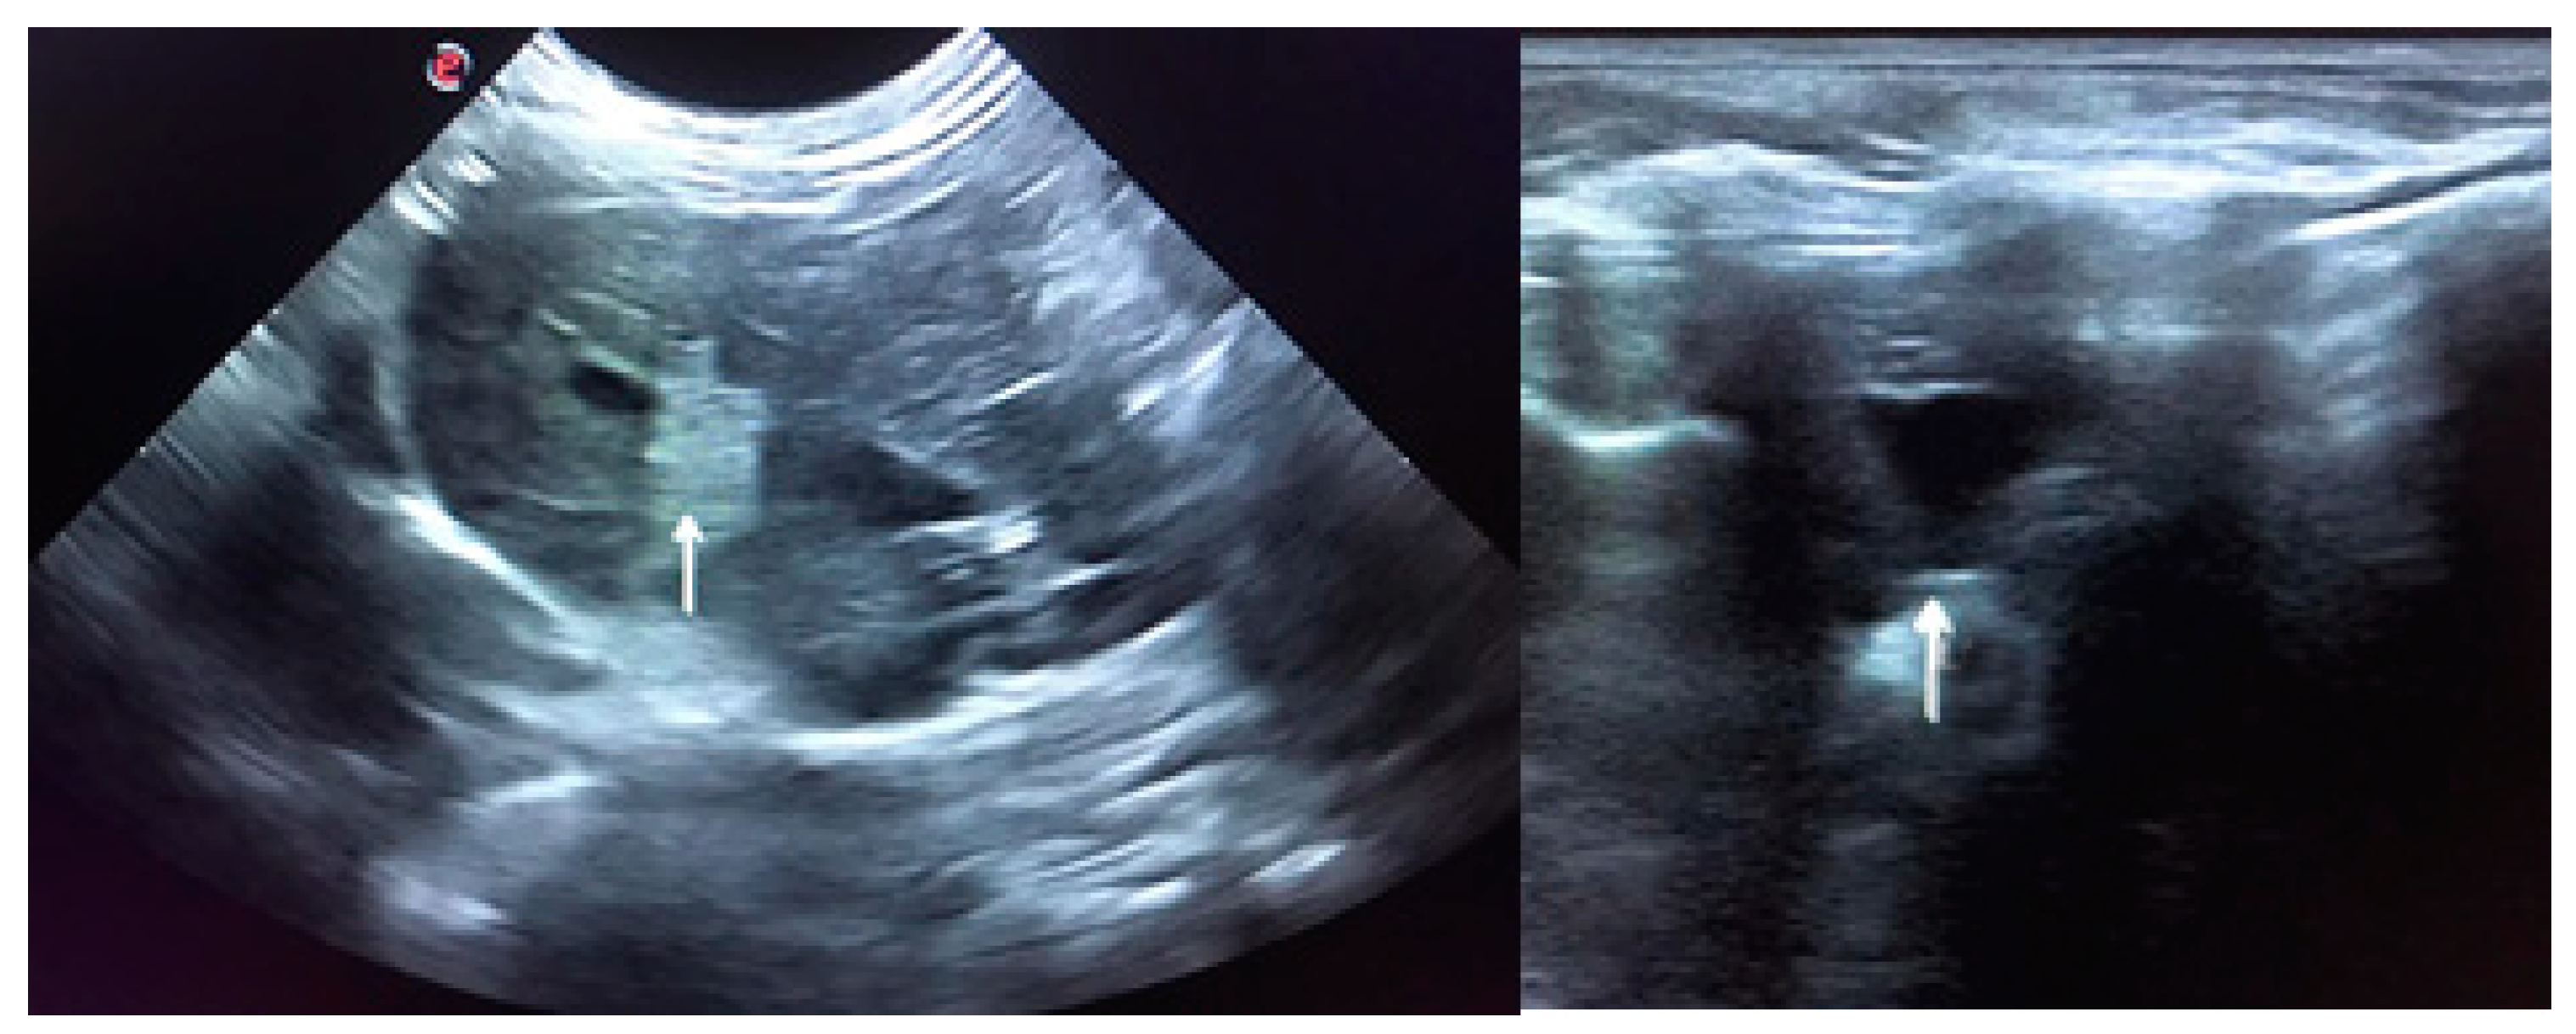

In June 2020, the rabbit was readmitted due to anorexia, lethargy, coprostasis and abdominal discomfort. The rabbit had lost 80 g, weighting then 1420 g, and for the first time, mildly hyperthermia (39.4 °C) was registered. The blood panel revealed severe leukopenia (1.86 K/μL) associated with heteropenia (0.89 K/μL) and lymphopenia (0.78 K/μL). Thrombocytopenia (97 K/μL) was also observed. ALT was then 586 U/L and there was also the elevation of total bilirubin (0.9 mg/dL) and total proteins (7.7 g/dL) due to hyperglobulinemia (3.3 g/dL) (Table 1). The blood draw resulted once again in cutaneous haemorrhagic dyscrasia and therefore the rabbit was started on vitamin K1 (10 mg/kg SC BID), enrofloxacin (5 mg/kg SC SID), buprenorphine (0.03 mg/kg SC TID), metoclopramide (0.5 mg/kg SC BID), lactulose (0.5 mL/kg PO BID) and aggressive fluid therapy. Ultrasound was compatible with severe hepatitis and peri-lobular peritonitis (Figure 2), with mesenteric reactivity and free fluid in the abdomen. The rabbit was in the hospital for 3 days showing no signs of improvement. The temperature kept increasing reaching a peak of 40.2 °C on the second day of hospitalisation, after which it started dropping and the rabbit became progressively hypothermic. On the 3rd day of hospitalization, the temperature dropped to 36.9 °C, despite the active heating efforts. The rabbit became lethargic, jaundiced and developed vertical nystagmus. The death occurred about 6 h after the onset of these symptoms.

Figure 2. Ultrasound is compatible with hepatitis. The image on the left shows peri-lobular mesenteric reactivity (arrow). On the right, free fluid in the abdomen is visible (arrow).